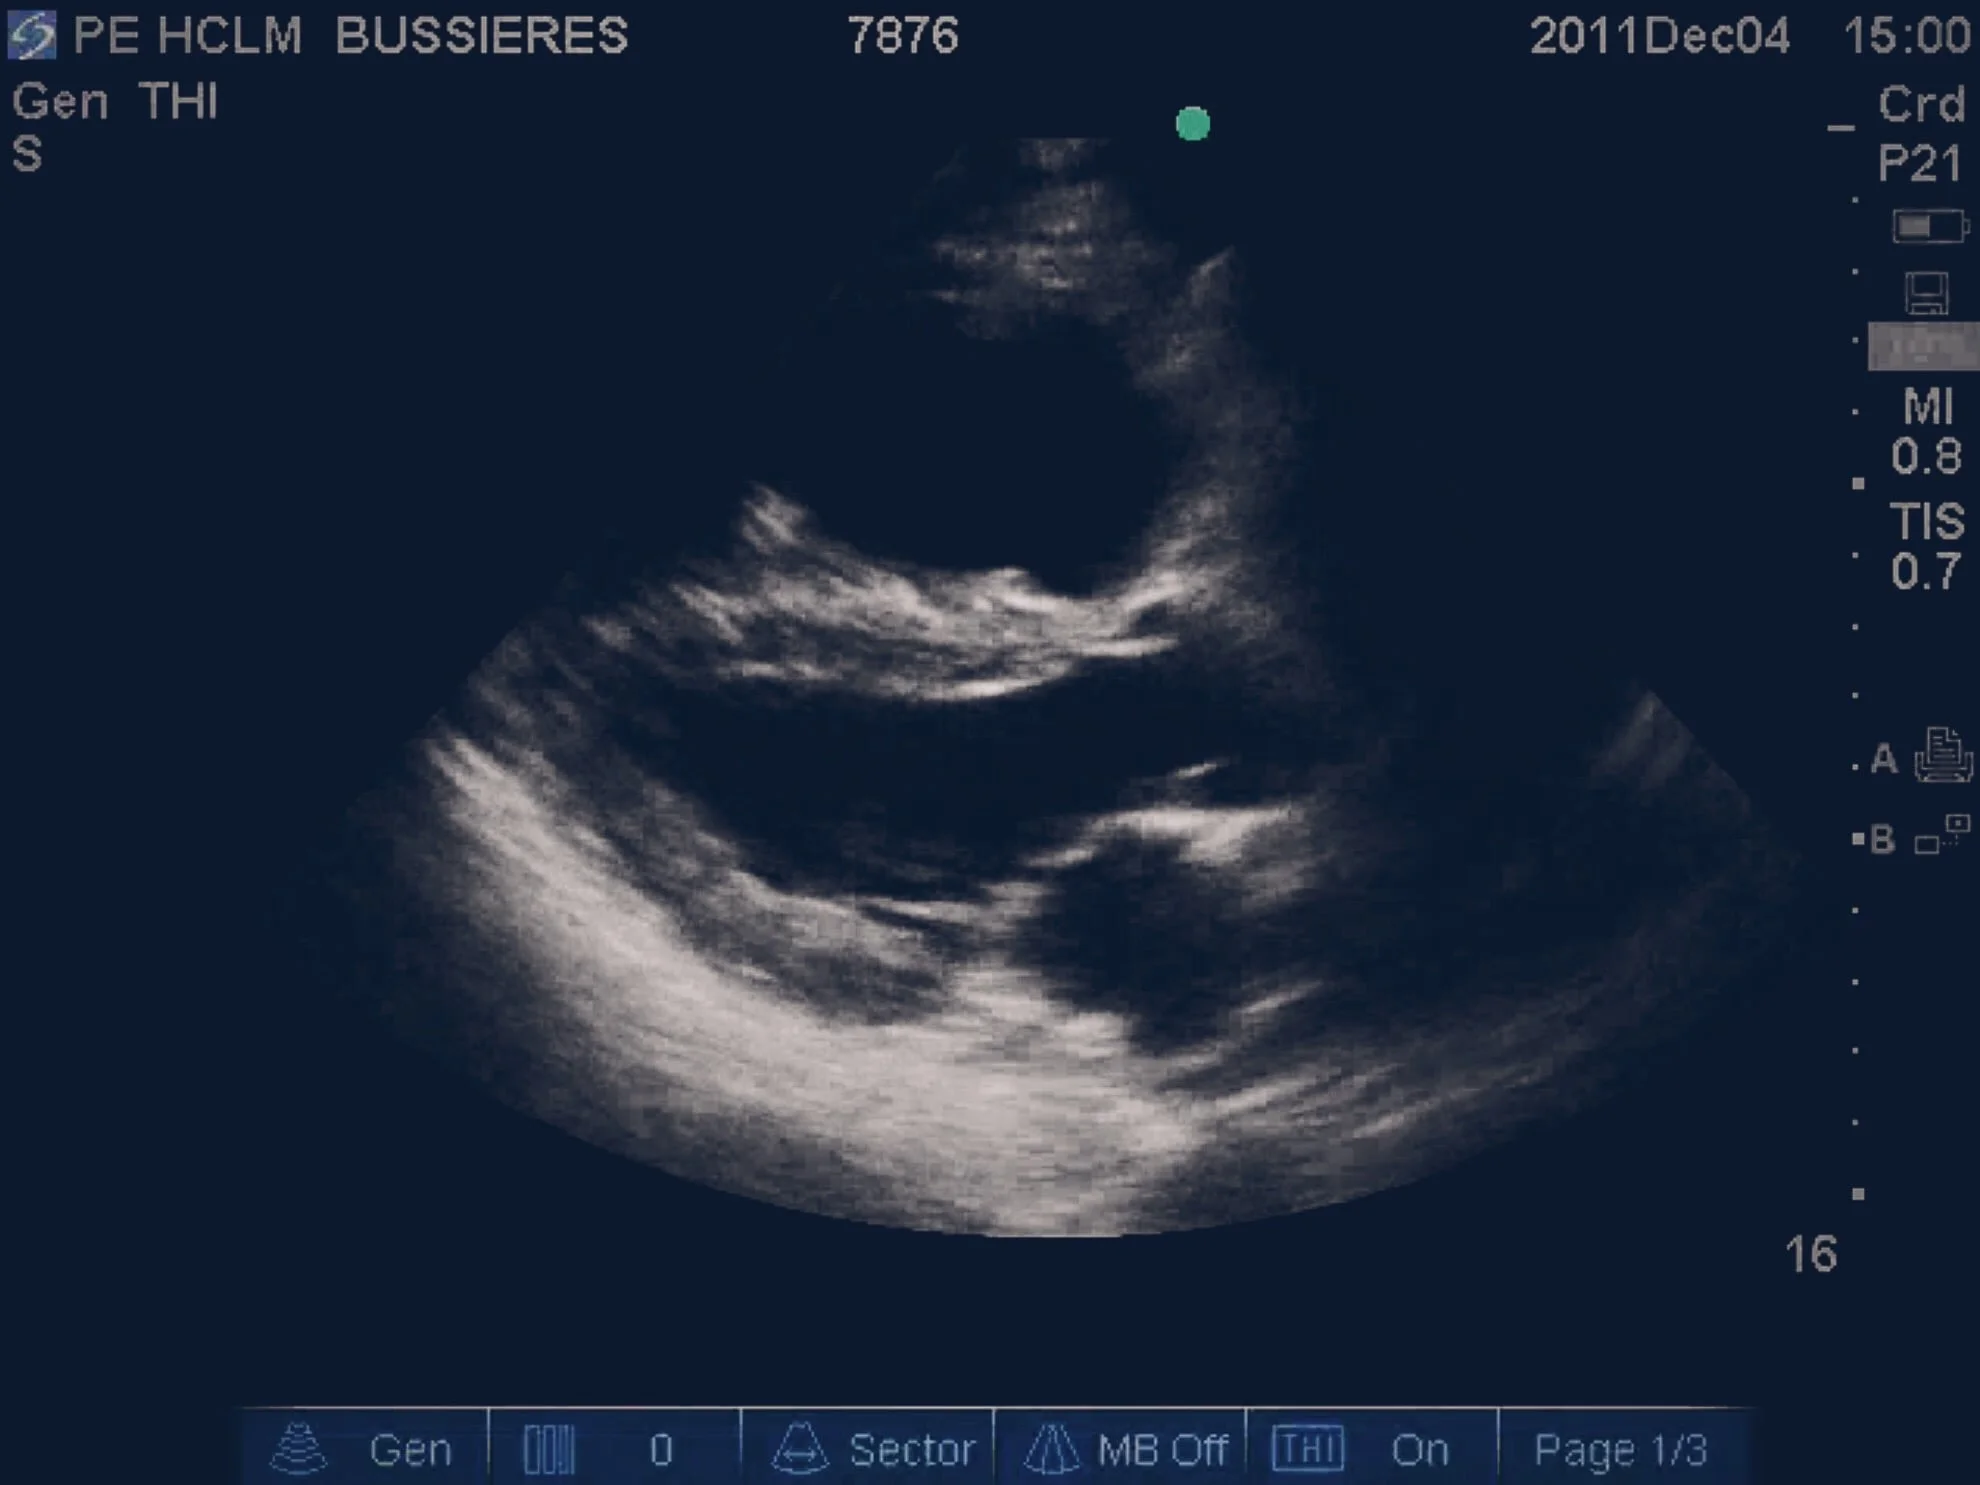

86 y/o female. Fall from standing hitting her chest against a set of drawers. Has been on the floor for 24 hrs.